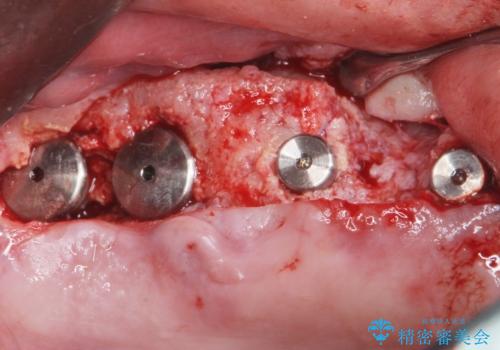

禁煙指導と歯周病治療後、右上臼歯部のソケットリフト及びインプラント治療(右上7654埋入)を行いました。

右上6欠損部の骨が極端に薄くアバットメント装着後に動揺が出たため、右上6フィクスチャーは除去しております。

(手術時に生着しない可能性を予見し患者様にも事前に説明を行っておりました。)